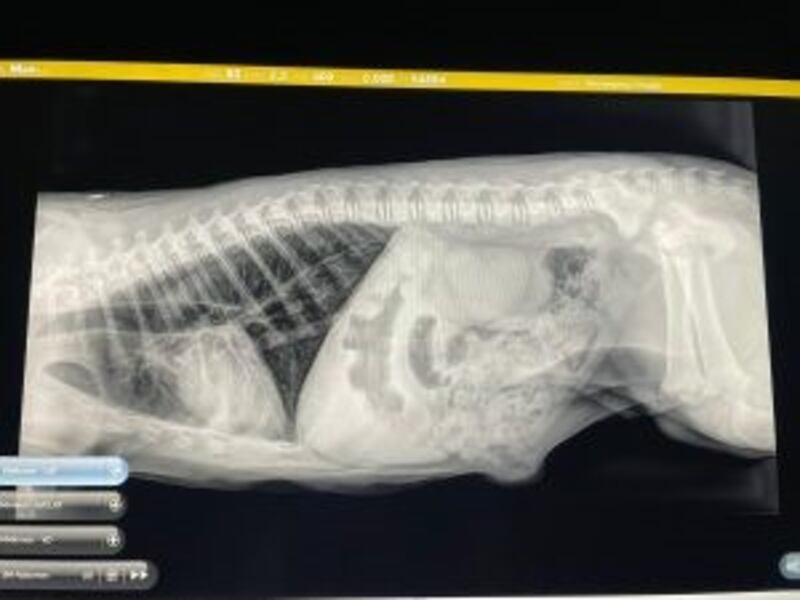

Just as it seemed the nightmare may be coming to an end for this group of African lions — a dangerous revelation. “The single cat had six cubs in her that were all about two weeks overdue, and so it was it was a recipe for disaster,” said Thies of Wildcat Sanctuary.